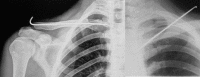

Treatment of clavicle fractures

Clavicle fractures are very common injuries in adults (2-5%) and children (10-15%) (1) and represent the 44-66% of all shoulder fractures (2). Despite the high frequency the choice of proper treatment is still a challenge for the orthopedic surgeon. With this review we wants to focus the attention on the basic epidemiology, anatomy, classification, evaluation and management of surgical treatments in relationship with the gravity of injuries. Both conservative and surgical management are possible, and surgeons must choose the most appropriate management modality according to the biologic age, functional demands, and type of lesion. We performed a review of the English literature thought PubMed to produce an evidence-based review of current concept and management of clavicle fracture. We finished taking a comparison with our survey in order to underline our direct experience.